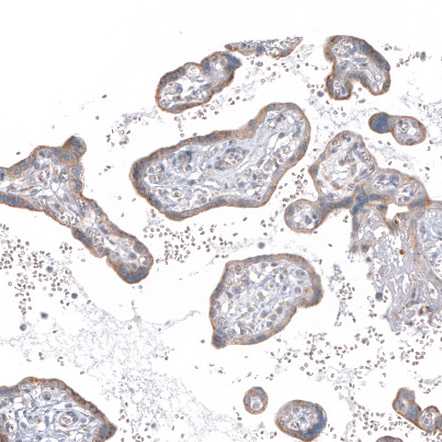

Immunohistochemical staining of human testis shows moderate granular cytoplasmic positivity in cells in seminiferous ducts.